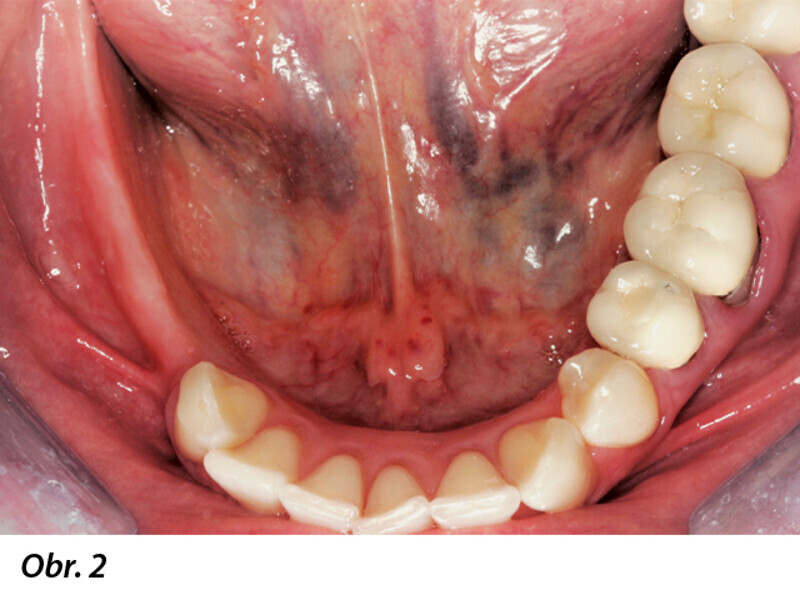

Horizontální augmentace hřebene a implantace: Dvoufázová procedura GBR